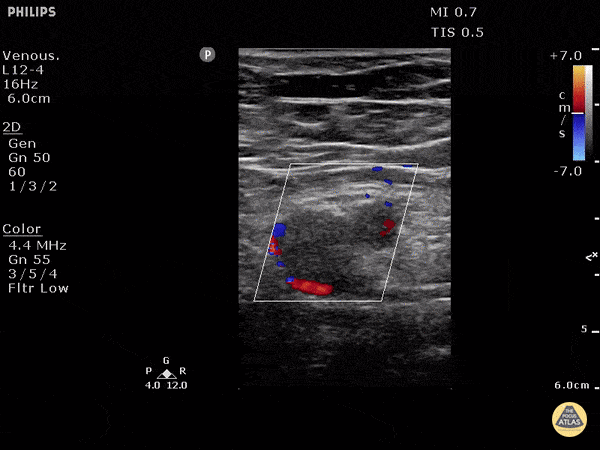

Vascular - DVT of Left Common Femoral Vein

Patient with profound rapid onset lower extremity pain and swelling. POCUS can be used to rapidly assess for DVT with as high as 95% sensitivity and 96% specificity amongst ED providers. In this image the artery can be seen as the pulsating thick walled vessel with strong pulsations under color doppler. The vein is the large vessel with echogenic material with flow only around the edge of the clot. Inability to compress the vessel would confirm the diagnosis of DVT (not pictured). Dr. Justin Bowra et al.